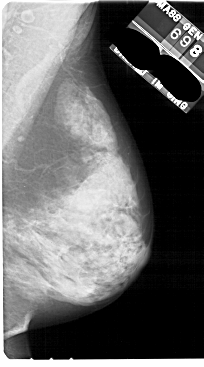

A_1844_1.LEFT_MLO

LEFT_MLO LINES 5491 PIXELS_PER_LINE 3406 BITS_PER_PIXEL 12 RESOLUTION 43.5 OVERLAY